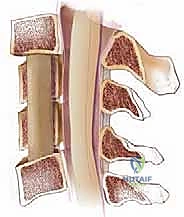

الخطوة 3: استئصال الأقراص الغضروفية وجسم الفقرة (Corpectomy)

باستخدام الميكروسكوب الجراحي وأدوات دقيقة جداً، يتم أولاً إزالة الأقراص الغضروفية أعلى وأسفل الفقرة المستهدفة. بعد ذلك، يتم استئصال جسم الفقرة العظمي المتضرر بعناية فائقة لفتح مساحة واسعة وتحرير الحبل الشوكي المضغوط.

الخطوة 4: زراعة الدعامة والدمج العظمي (Fusion)

بعد إزالة الفقرة، يتبقى فراغ كبير. لإعادة بناء العمود الفقري، يتم إدخال دعامة معدنية أو قفص من مادة (PEEK) أو التيتانيوم، مملوء بطعم عظمي (يؤخذ عادة من بنك العظام أو من حوض المريض، أو يتم استخدام بدائل عظمية صناعية). هذه الدعامة تحافظ على ارتفاع الرقبة الطبيعي.